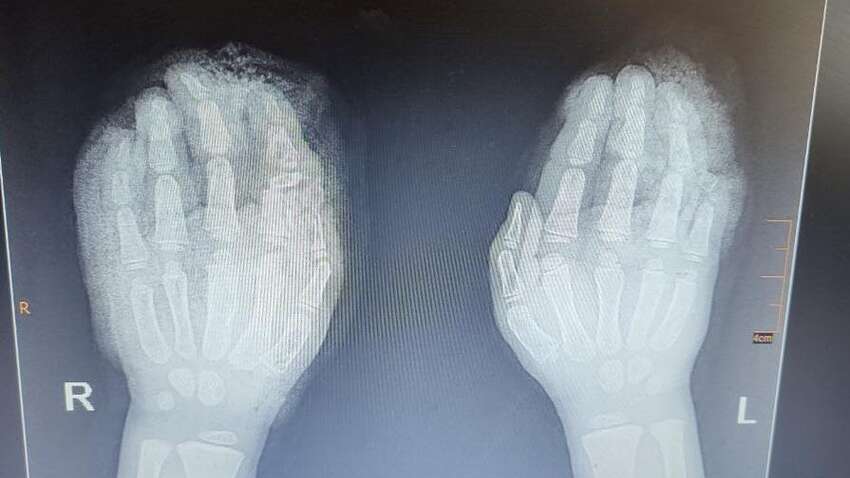

Во Львовской областной детской больнице "Охматдет" медики провели серию сложных операций, чтобы спасти руки пятилетнего мальчика. Он получил тяжелые травмы в результате несчастного случая с соломорезкой во время сельскохозяйственных работ.

Мальчик на Львовщине травмировал одну руку, когда она попала в соломорезку — машину для измельчения корма. Пытавшись вытащить ее, он инстинктивно использовал вторую, также застрявшую в механизме. В результате этого ребенок получил тяжелые травмы, а именно:

По словам врачей, травмы были настолько серьезными, что пришлось собирать пальцы по частям. Обломки костей фиксировали специальными спицами. Из-за частичной потери кожи на одном из пальцев понадобилась еще одна операция, заключавшаяся в трансплантации кожи с передней поверхности бедра, проведенная с помощью дерматомного аппарата.